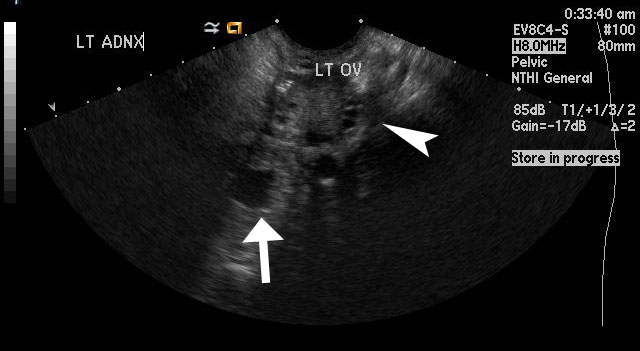

Figure 2

This image shows left adnexal ectopic pregnancy with the arrow pointing towards the anechoic gestational sac, which is separate from the left ovary (arrowhead). |